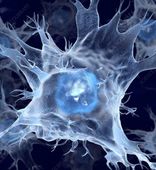

Институт биофизики и клеточной инженерии НАН Беларуси занимается разработкой биомедицинских клеточных продуктов (БМКП) — на данную деятельность учреждение имеет все необходимые документы. БМКП используются при лечении онкологических, неврологических и аутоиммунных заболеваний.

На базе Института действует отделение клеточной терапии (ОКТ): именно здесь занимаются диагностикой и лечением непростых заболеваний с использованием современных методик, в основе которых лежат клеточные технологии. ОКТ предоставляет медицинские услуги в области аллергологии и иммунологии, онкологии и лабораторной диагностики.